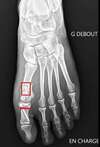

Même patiente : bilan radiographique

-

Chirurgie 1 an plus tôt côté droit

Hallux Valgus avant pied gauche : radiographie en charge de Face

même patiente après chirurgie : en rouge zone d'ostéotomie

même patiente après chirurgie : en rouge zone d'ostéotomie (vue de profil en charge)